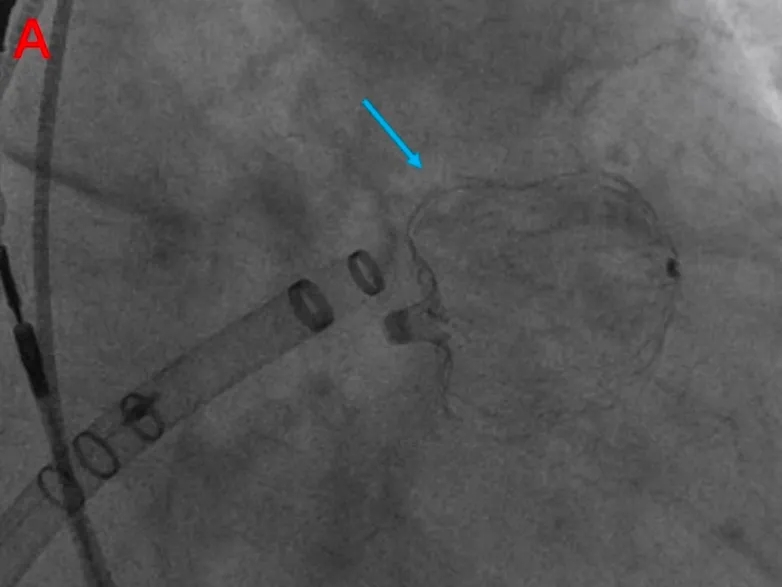

选择27mm Watchman FLX(Boston Scientific)左心耳封堵器,置入顺利,位置良好,压缩比合适,无残余漏,牵拉试验稳定。完成后交换输送鞘,选择D‐Shufo(Vickor)卵圆孔封堵器(30mm),完全覆盖ASA与PFO,TEE无残余分流。

成功置入左心耳封堵器

成功置入PFO封堵器